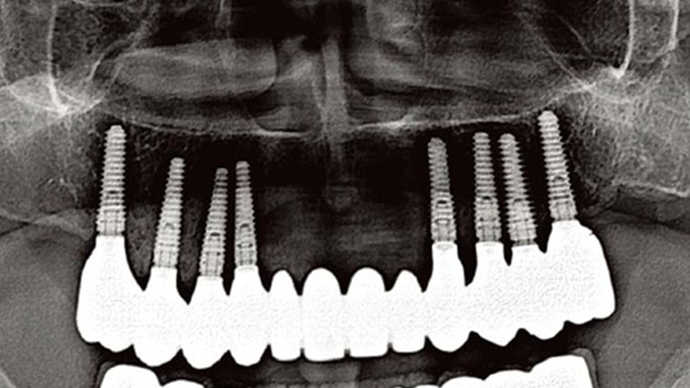

Clinical case: Advantage of fuse abutment with AnyRidge implant for immediate loading in

upper fully edentulous case

- Courtesy of Dr. Kwang Bum Park -

“AnyRidge shows excellent initial stability

& stable results after immediate loading in

upper fully edentulous case. ”